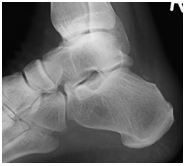

Auf dem Röntgenbild zeigt sich die fortgeschrittene Arthrose des Großzehengrundgelenkes. Der Knorpel ist vollkommen zerstört (Pfeil). Es reibt Knochen auf Knochen, was die Schmerzen verursacht.